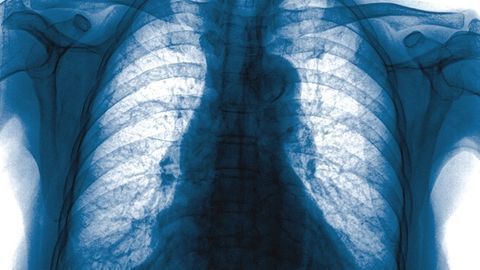

In high pre-test probability and quick RT-PCR settings, chest X-ray scoring can be predictive.

Pairing machine learning methods with chest X-rays can potentially improve viral detection in areas where access to swab testing and chest CT scans is inadequate.

Chest X-ray and Chest CT for TB Detection; Contrast-Enhanced Mammography for Women with Breast Implants; Risk-Based Approach to Optimizing Mammography During Crisis; Plus, Natural Language Processing for COVID-19 Case Volume Prediction

Decline in number of TB cases is slowing in the United States, making timely identification critical.